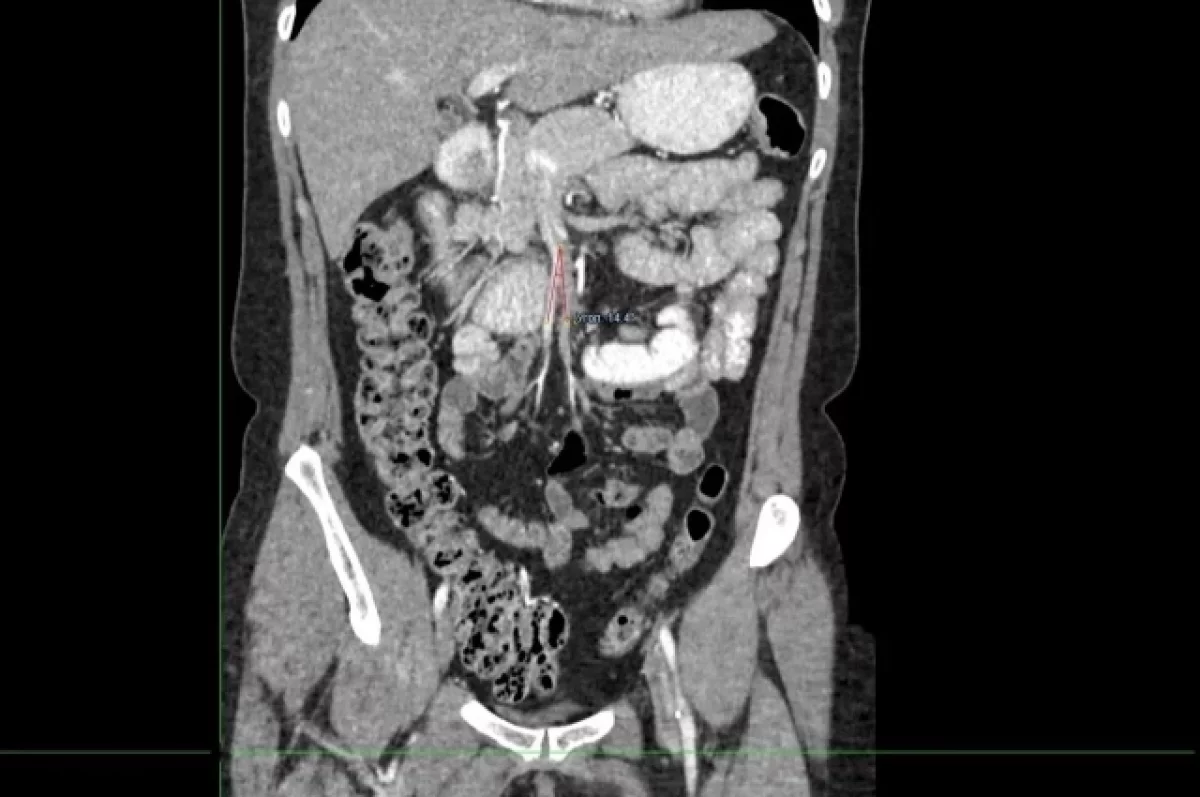

Красноярку с редким заболеванием Уилки прооперировали хирурги 20-й больницы

49-летняя красноярка долгое время страдала от редкого синдрома Уилки. Женщина не могла полноценно есть и из-за этого сильно похудела. Известно о не более 500 случаях этого заболевания.

Помочь пациентке взялись врачи хирургического отделения № 3 Красноярской межрайонной клинической больницы № 20 им И.С. Берзона. Хирурги провели манипуляции щадящим методом. Операция длилась три часа. После операции на третьи сутки женщина почувствовала облегчение и начала есть самостоятельно. Сейчас пациентка восстанавливается дома.